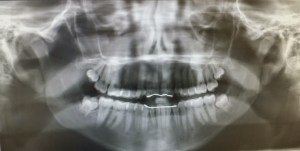

My 18 year old daughter had her wisdom teeth taken out recently. She has permanent retainers on both her upper and lower jaws. On one side of her jaw the wisdom teeth were partially impacted, while on the other side the wisdom teeth were fully impacted. This would cause her surgery to be slightly difficult and rather painful. We were told that one side of her face could bruise more and would be swollen more then the other side.